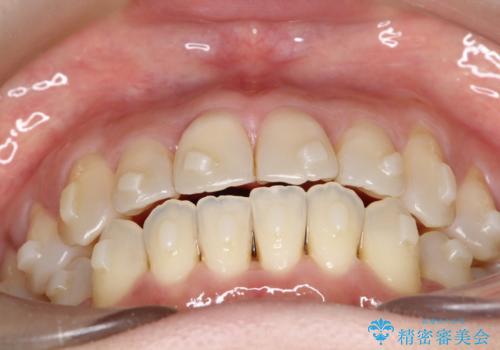

【開咬】笑った時の見た目を改善したい。

- 重度の開咬でしたがインビザラインで適切に治療計画を立て、きれいに仕上がりました。